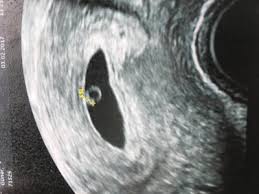

Ultraschall schwangerschaft 6. woche. Schwangerschaft - 6. Eindeutig erkennbar ist das pulsierende Herz aber meistens erst in zwei bis drei Wochen. Schwangerschaftswoche 8 0 bis 11 6 SSW 1Screening 18 0 bis 21 6 SSW 2Screening 28 0 bis 31 6 SSW 3Screening.

Schwangerschaftswoche sind auch die Struktur des Embryos und sein Herzschlag zu erkennen. Eine frühe Ultraschalluntersuchung dient vor allem dazu die Schwangerschaft zu bestätigen und eine Eileiterschwangerschaft auszuschließen. Die Entwicklung des Embryos schreitet nun rasant voran.

SSW Details zu Entwicklung des Babys der erste Ultraschall Schwangerschaftssymptome Tipps zur Linderung uvm. Vom Bauch des Embryos aus führt die Nabelschnur in der sich nun Blutgefäße zum Transport der Nährstoffe bilden zur Plazenta. Ist Dein Gynäkologe mit entsprechender Technik ausgestattet kann er die Schwangerschaft in der 6.

Von einer auf die andere Woche hat dein Baby seine Größe verdoppelt. SSW zum ersten Mal den Herzschlag deines Babys am Ultraschall. Im Lauf der kommenden Wochen bildet sich ein primitives Kreislaufsystem Im Verlauf der Schwangerschaft werden drei Ultraschall-Untersuchungen Ultraschall-Screening angeboten.

SSW bereits vorhanden im Ultraschall sind am Kopf die Anlagen für Augen Ohren und Gehirn zu erkennen. Im Ultraschall kann man den Puls dieser Blutgefäße beobachten.